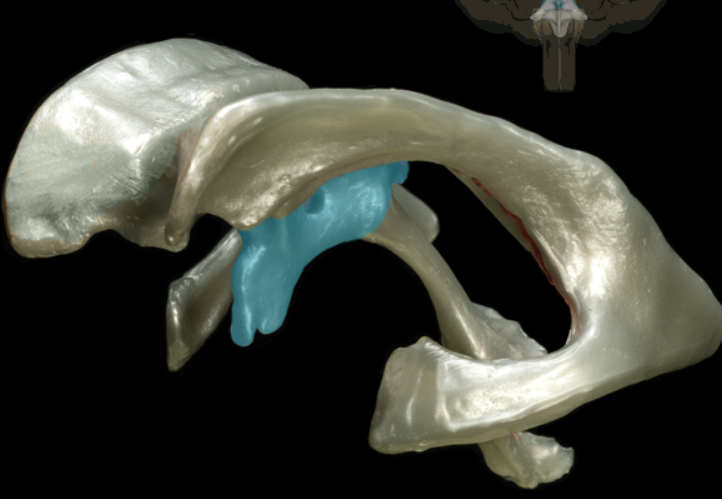

tentorium cerebelli